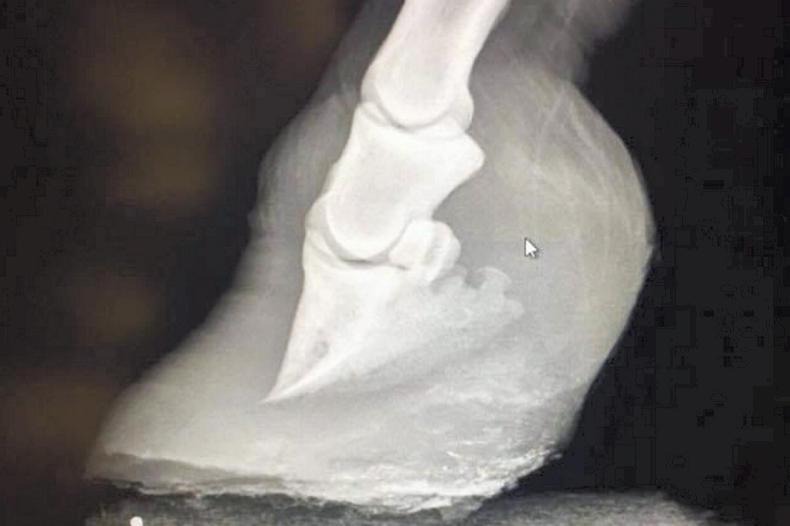

The local vet, Kieran Cronin of All Creatures Veterinary Group, had attended the pony earlier that day and had carried out X-rays of the pony’s front feet to confirm that there was a rotation of the distal phalanx (see X-ray below), before referring the horse owner to me for treatment.

Rotation of the distal phalanx indicates chronic laminitis.

The images below show the pony's feet before being treated by Master Farrier, Breen Concannon